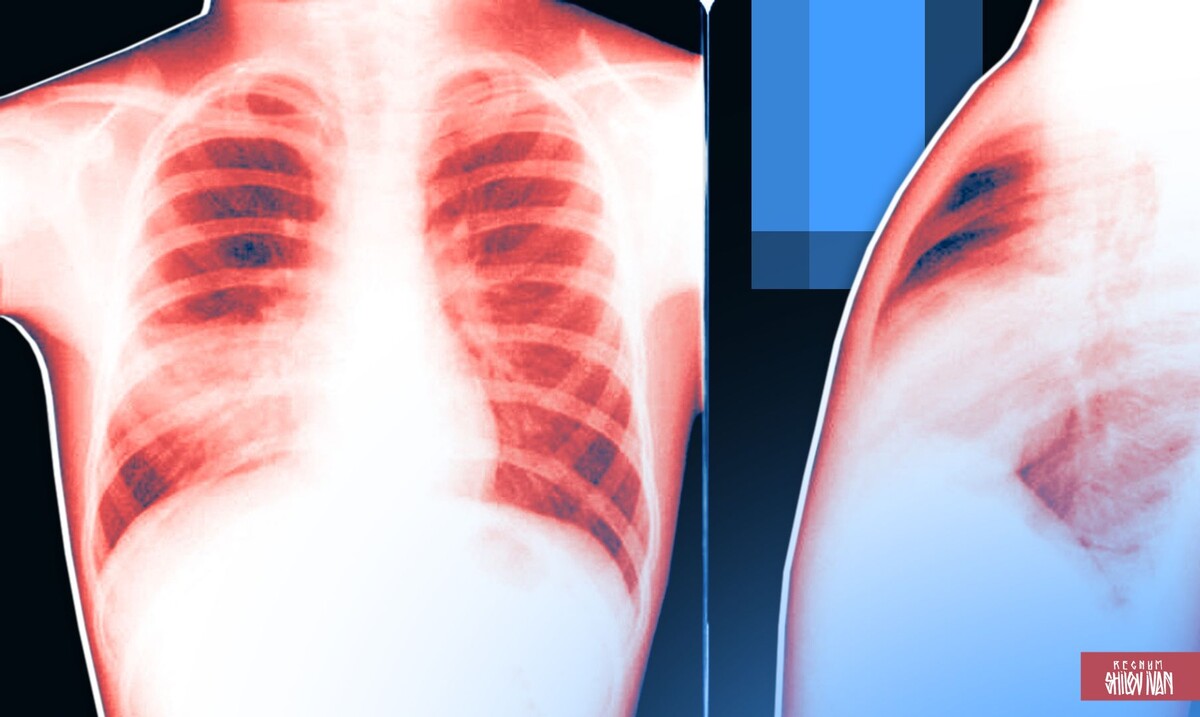

Роспотребнадзор перечислил основные симптомы пневмонии

/ Источник: Иван Шилов (с) ИА Регнум